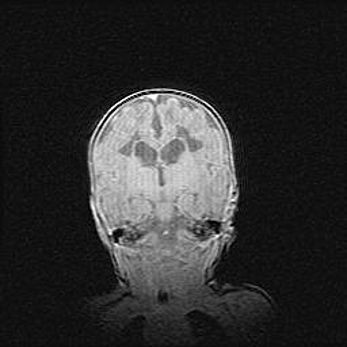

Множественные кисты обоих полушарий головного мозга, наибольшая из них в правой затылочной области. Ассиметричная атрофическая гидроцефалия.

Возраст: 7 месяцев

Вес: 5660 г

Пол: мужской

Окружность головы: 41,5 см

Срок гестации: 28-29 недель

Кисты головного мозга развиваются в результате многоочаговых некрозов вещества мозга и возникают вследствие перенесенной перинатальной инфекции, менингитов, энцефалитов, асфиксии, родовой травмы, расстройств мозгового кровообращения различного генеза. Образованию кист в веществе головного мозга плодов и новорожденных способствуют такие факторы, как высокое содержание в нем воды, недостаточная (или отсутствие) миелинизация и слабая астроглиальная реакция на повреждение.

Кисты могут сочетаться с гидроцефалией и другими поражениями головного мозга.